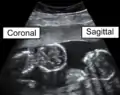

Coronal plane

The coronal plane (also known as the frontal plane) is an anatomical plane that divides the body into dorsal and ventral sections. It is perpendicular to the sagittal and transverse planes.

The coronal plane is an example of a longitudinal plane. For a human, the mid-coronal plane would transect a standing body into two halves (front and back, or anterior and posterior) in an imaginary line that cuts through both shoulders. The description of the coronal plane applies to most animals as well as humans even though humans walk upright and the various planes are usually shown in the vertical orientation.